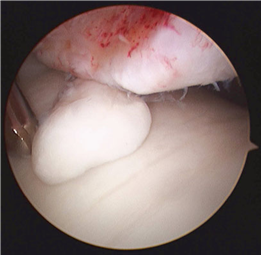

Conversely, hallux rigidus represents a degenerative cascade characterized by osteophyte formation, dorsal impingement, and progressive loss of sagittal plane motion at the first MTP joint. While trauma and inflammatory arthropathies can precipitate this condition, the most common etiology is idiopathic, often linked to an elevated or elongated first metatarsal (metatarsus primus elevatus), which alters the joint's instant center of rotation and accelerates articular wear. Recognizing these distinct pathophysiological pathways is paramount for the orthopedic surgeon, as it dictates the selection of joint-sparing osteotomies versus joint-sacrificing arthrodesis.

| Cheilectomy | Coughlin/Shurnas Grade 1 or 2 hallux rigidus; Dorsal impingement pain with preserved plantar cartilage. | Grade 4 hallux rigidus (diffuse joint space narrowing); Severe angular deformity. | Systemic inflammatory arthropathy (e.g., Rheumatoid arthritis). |

First MTP Arthrodesis

In cases of end-stage hallux rigidus, first MTP arthrodesis yields excellent, predictable outcomes. A dorsal longitudinal incision is made just medial to the EHL tendon. The joint is exposed, and aggressive cheilectomy is performed to remove all dorsal, medial, and lateral osteophytes. The remaining articular cartilage on the metatarsal head and the base of the proximal phalanx is resected using cup-and-cone reamers, which allow for infinite adjustment of the joint position prior to fixation.

Positioning of the fusion is the most critical step of the operation. The hallux must be positioned in 10-15 degrees of valgus, 15-20 degrees of dorsiflexion relative to the first metatarsal, and neutral rotation. Excessive dorsiflexion causes shoe impingement, while insufficient dorsiflexion leads to vaulting during gait and interphalangeal joint arthritis. Fixation is most reliably achieved using a pre-contoured dorsal locking plate combined with a lag screw crossing the fusion interface.